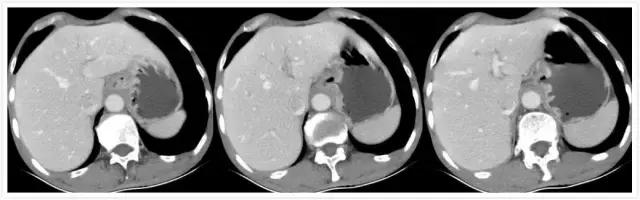

患者男性68岁,主因消瘦2个月,腹部不适入院就诊。详细检查报告及影像资料如下:

中晚期胃底贲门腺癌,诊断已明确。治疗方案有